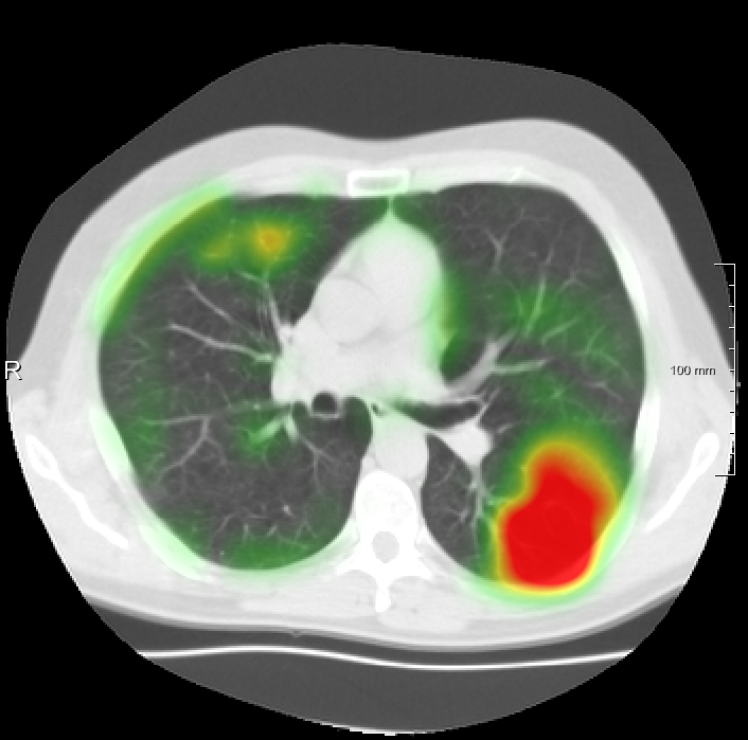

In total we generate 14 basis types of artificial DVFs: 5 single frequency, 4 mixed frequency, 4 respiratory motion and 1 identity. The precise settings of the parameters are available in Table I and examples are given in Fig. 4. The histograms of the Jacobians are also available in this figure. When the spatial frequency is increased, the Jacobian histograms will spread more, which shows that local relative volume changes are increased. The value of , the maximum artificial displacement along each axis, is chosen as 20, 15 and 7 for RegNet4, RegNet2 and RegNet1, respectively.

For the DIR-Lab-4DCT database, a comparison between RegNet and affine, B-spline (three resolutions), an advanced conventional registration method using sliding motion (Berendsen et al., 2014) and three other CNN-based methods (Eppenhof and Pluim, 2018; de Vos et al., 2019; Sentker et al., 2018) is available in Table IV. It can be seen that training with “S+M” improved performance slightly with respect to just “S”. Adding the respiratory motion category improved performance substantially, as these are inhale-exhale pairs; this is predominantly caused by the patients where the TRE after affine registration was still quite large. An example visualization is also available in Fig. 5(f), showing that adding the respiratory motion category can align images better in the diaphragm region. The advanced conventional registration method that leverages sliding motion (Berendsen et al., 2014) is still better than RegNet. Note that RegNet was not trained on the DIR-Lab-4DCT data, similar to Eppenhof and Pluim (2018); Sentker et al. (2018). However, de Vos et al. (2019) and Eppenhof and Pluim (2018)-DIR methods were trained on the same database but using cross-validation to report the results. Also note that the results reported in Sentker et al. (2018) are averaged over all phases of DIR-Lab-4DCT (T00 to T10), while the results of other CNN methods (including RegNet) are reported between the maximum inhale and maximum exhale phase (T00 and T50). These reported results are therefore likely somewhat better than the results for T00 and T50 only.